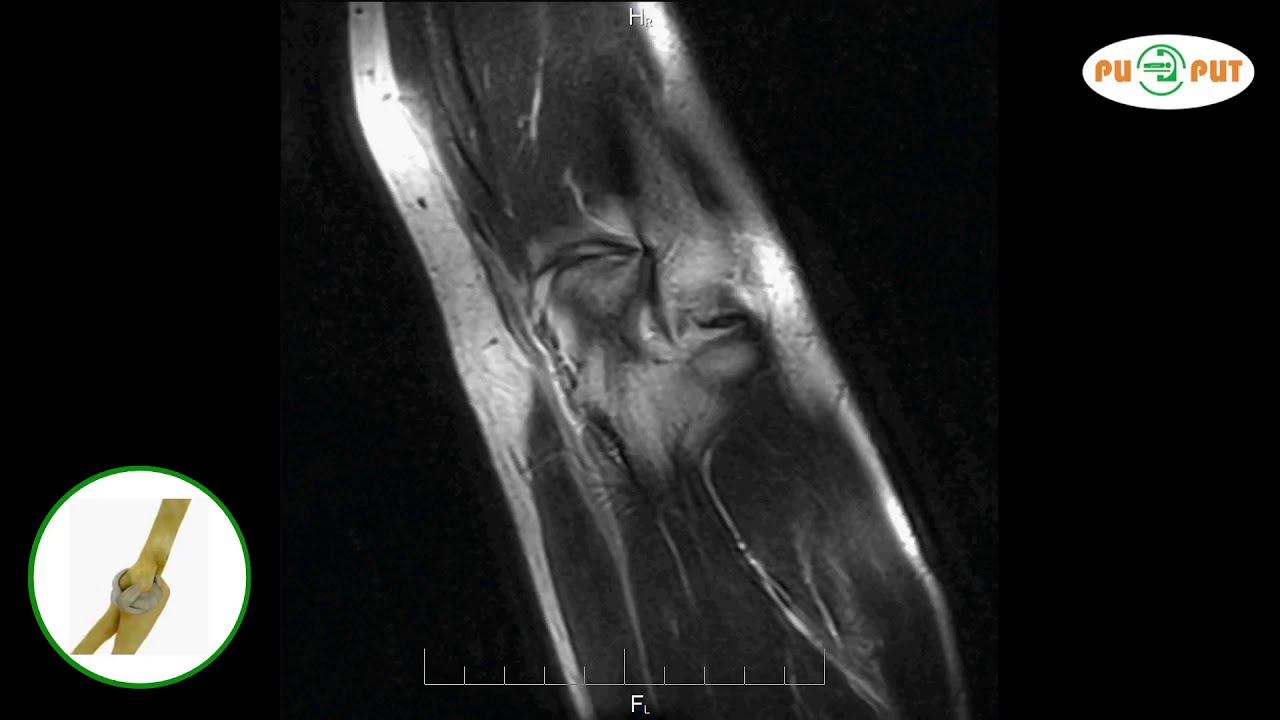

На фото ниже представлены различные виды патологий локтевого сустава.

Рентгенограмма локтевого сустава является важным инструментом в диагностике различных заболеваний и травм. Врачи отмечают, что этот метод позволяет визуализировать костные структуры, выявлять переломы, вывихи и другие повреждения. На снимках можно увидеть изменения в суставных поверхностях, которые могут указывать на артрит или остеоартроз. Специалисты также подчеркивают, что рентген помогает оценить состояние мягких тканей, хотя для более детального изучения может потребоваться МРТ или УЗИ. Важно, что правильная интерпретация рентгенограмм требует опыта и знаний, так как некоторые патологии могут быть неочевидны на первых снимках. Таким образом, рентгенография является незаменимым этапом в диагностическом процессе, позволяя врачам принимать обоснованные решения о дальнейшем лечении.